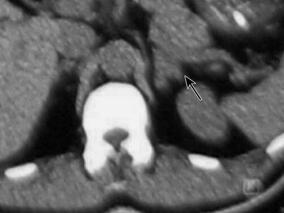

权威专家动脉溶栓联合机械取栓术治疗颈内动脉闭塞患…

1小时条评论1 病例简介 患者男,40岁,主因突发左侧肢体无力2小时于2011年3月30日入院。患者2小时前安静状态下无明显诱因出现左侧肢体无力,伴言语不清、不能行走、意识模糊。无视物旋转、视物成双、耳鸣、恶心、呕吐,无饮水呛咳及吞咽困难,无流涎,无肢体抽搐,无大小便失...